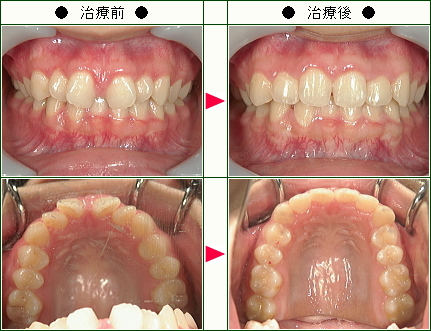

☆歯のデコボコ矯正症例(yayoi様 30歳 女性)